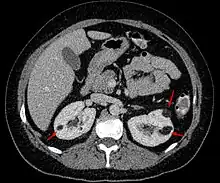

Examens d'imagerie

L'angiomyolipome est, dans la majorité des cas, une découverte de hasard lors d'un examen de l'abdomen par échographie, tomodensitométrie ou Imagerie par résonance magnétique.

- A la tomodensitométrie sans injection de produit de contraste il est de densité négative (UH<0, tonalité graisseuse) et se rehausse instantanément après injection (riche vascularisation).